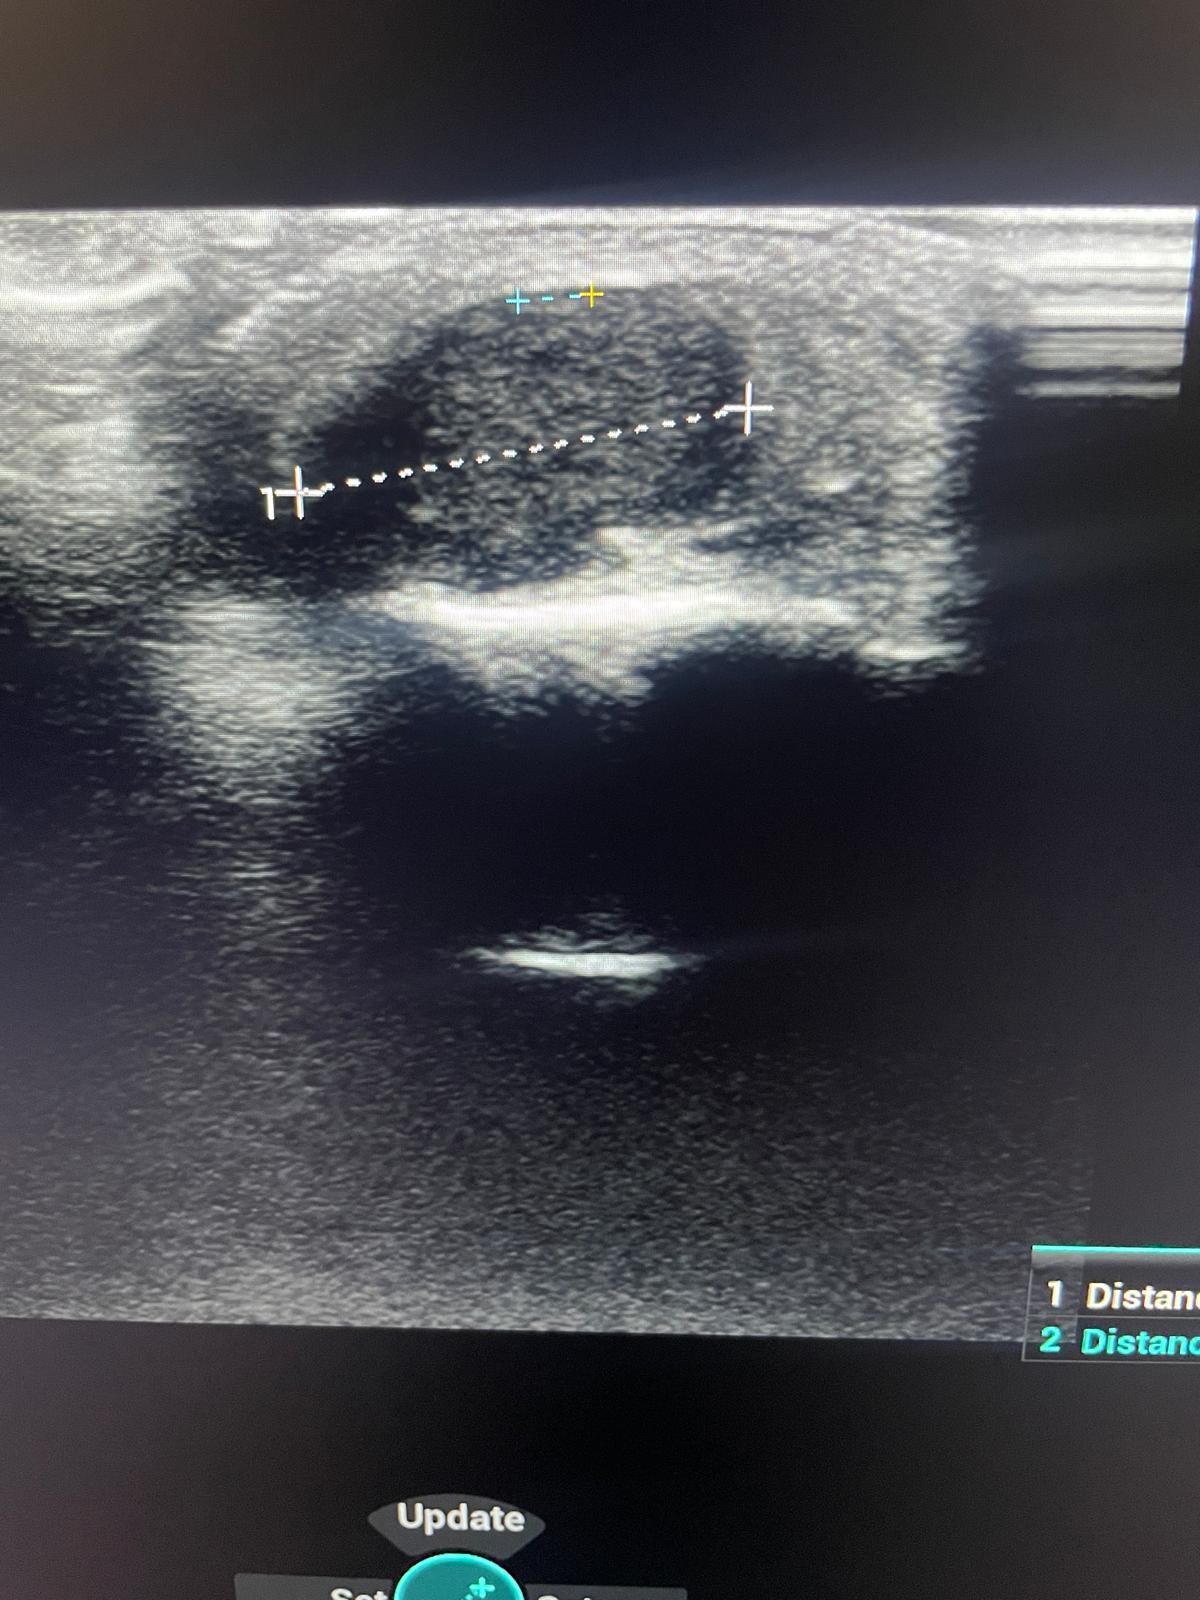

Refiere dolor en pulpejo de 1 dedo de mano derecha hace dos meses, que cree que se clavó una astilla en el jardín.Hallazgos ecográficos

Ecografía en Atención Primaria: nódulo heteroecoico (halo hipoecoico y centro hiperecoico), bien delimitado, que no capta Doppler.Pruebas complementarias